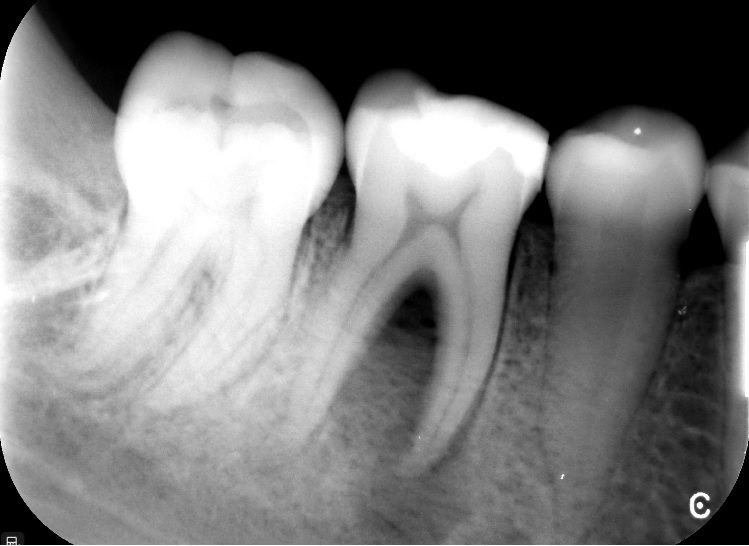

STRESZCZENIE: W pracy opisano przypadek leczenia endodontycznego stałego zęba trzonowego z przewlekłym ropnym zapaleniem tkanek okołowierzchołkowych. Terapię uzupełniono procedurą PAD z zastosowaniem niskoenergetycznego lasera diodowego. Przedstawiono kliniczny protokół tego postępowania. Po okresie rocznej obserwacji ząb pozostawał asymptomatyczny, a zmiany okołowierzchołkowe uległy wygojeniu.

SUMMARY: This paper describes a case of the endodontic treatment of a permanent molar with chronic purulent periapical tissue inflammation. The therapy was complemented with a PAD procedure using a low-energy diode laser. The clinical protocol for this procedure is presented. After a one-year follow-up period, the tooth remained asymptomatic, while the periapical lesions have been healed.